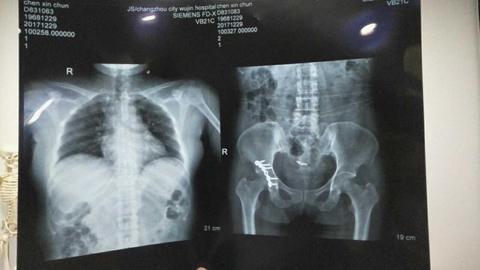

我叫陈新春,女,1968年3月出生,小学文化程度,江苏省盐城市射阳县人。2017年11月3日,在江苏省常州市新北区文化广场工地,八号楼二楼清理施工垃圾。因安全措施不到位,从6米高空施工洞坠入,造成颈椎骨折,脊柱骨折,腰椎L1一6横突骨折,腰椎右侧横突骨折,右侧髋臼,股骨头骨折装钢板,盆骨右侧L1一5骨折,左侧L1一5骨折,双侧耻骨折,左侧髋臼可疑骨折,腰椎至骨盆除左侧髋臼可疑骨折,全部骨折,外阴跌撕,胸椎骨折,内骨粉质性骨折,内骨右侧横突L1一4骨折,内骨左侧3一7两处骨折,右侧肋骨L1一10骨折,右侧肋骨后缘3一7两处骨折,左侧肋骨1.2.3.5.6.7.10骨折,后缘肩往下1一4两处骨折,左肩袖损伤肌健骨折;左冈上肌损伤,左肱骨因血液不流通,左肱骨长一个小圆形囊肿,腹部闭合性损伤,全身多处软组织损伤;双侧微量气胸,肝挫伤出血,脾挫伤出血,左肾挫伤出血,右肾上泉挫伤伴血肿,右肺上叶及两肺下叶挫伤出血,内腹部都挫伤出血。

这里所提供的几张片子拍出的颈椎骨折,腰椎横突骨,脊柱骨折,左侧盆骨骨折,内骨粉质性骨折,内骨左侧3一7两处骨折胸椎骨折,报告单都没有。报告单上有50根骨折包括两处有的,只出三分之一的骨折。常州市武进人民医院涉嫌隐瞒我的伤情,进手术室开刀涉嫌隐瞒了主要骨折的片子,去要片子不给;补出院小结,补两次,颈椎骨折,腰椎骨折,胸椎骨折,内骨粉质性骨折还不肯补。